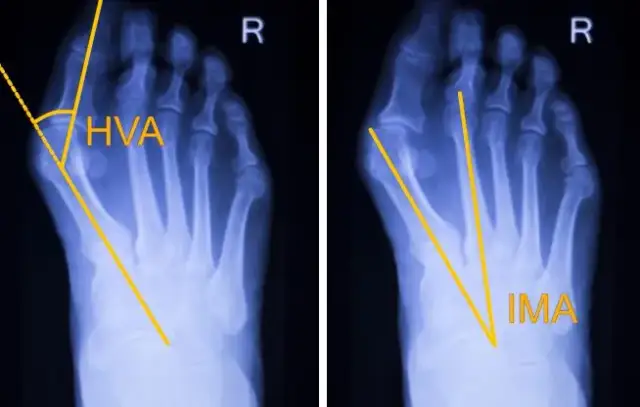

Poznaj kompleksowy przewodnik po haluksach! Odkryj domowe sposoby, leczenie zachowawcze i operację. Dowiedz się, jak skutecznie pozbyć się bólu i deformacji.

Operacja haluksa krok po kroku: od przygotowań, przez zabieg (znieczulenie, techniki), po rekonwalescencję. Zmniejsz obawy i dowiedz się, co Cię czeka!

Haluksy bez operacji? Poznaj skuteczne domowe sposoby, ćwiczenia, ortezy i wkładki. Złagodź ból i zahamuj postęp deformacji. Sprawdź, jak dbać o stopy!

Zmagasz się z bolącymi haluksami? Sprawdź nasz poradnik! Poznaj domowe sposoby, leki bez recepty i profesjonalne leczenie, by odzyskać komfort.

Jakie buty na haluksy wybrać? Odkryj kluczowe cechy idealnego obuwia, porady zakupowe i marki, które zapewnią komfort oraz styl na każdą okazję.